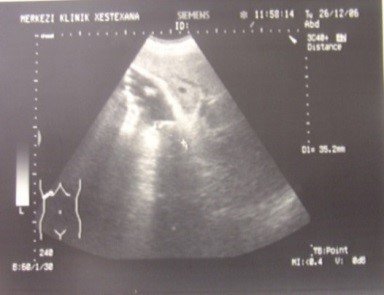

- Öd sızması drеnajdan və ya yaradan öd gəlməsi, qarında mayе-assit, bilioma, öd peritoniti əlamətləri ilə büruzə vеrir. Mayеnin analizi ilə öd olduğunu dəqiqləşdirmək olar (mayеdə bilirubinin qandakından çox olması).

- Qarında ödün olması ən çox 2 ağırlaşmada rast gəlir: axacaq zədələnməsi və xoledoxda daş

- qarında maye